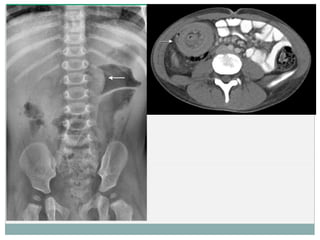

 Rx:

 S : 48% y E : 21%

 Sospecha o excluir perforación ( tto quirúrgico).

 No se debe realizar para excluir la invaginación intestinal,

sobre todo en pacientes con una clínica sugestiva.

 TC:

 Dx incidental (postqx).

 Otras técnicas no reveladoras.

 Plan quirúrgico/ caracterización de la lesión.

DIAGNÓSTICO (TÉCNICAS DE IMAGEN) Rx:  S : 48% y E : 21%  Sospecha o excluir perforación ( tto quirúrgico).  No se debe realizar para excluir la invaginación intestinal, sobre todo en pacientes con una clínica sugestiva.  TC:  Dx incidental (postqx).  Otras técnicas no reveladoras.  Plan quirúrgico/ caracterización de la lesión.